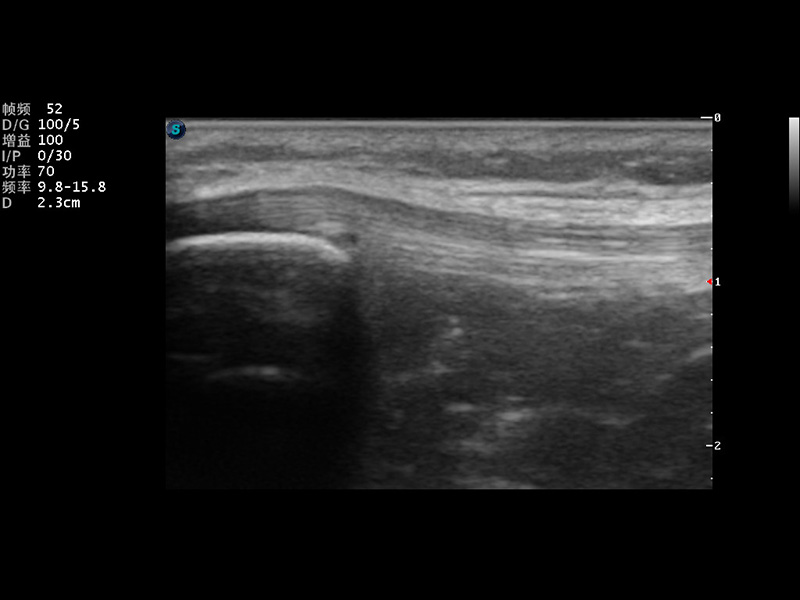

S9便携式彩色多普勒超声诊断仪是美狮贵宾会官网研发的高端便携彩超设备,外观设计新颖、产品性能卓越。S9在便携超声领域采用了突破传统的触摸屏交互设计,并以先进的软件硬件技术和设计理念,为您带来清晰的图像质量、稳定的工作性能和便捷的操作体验。

μ-Scan微米成像